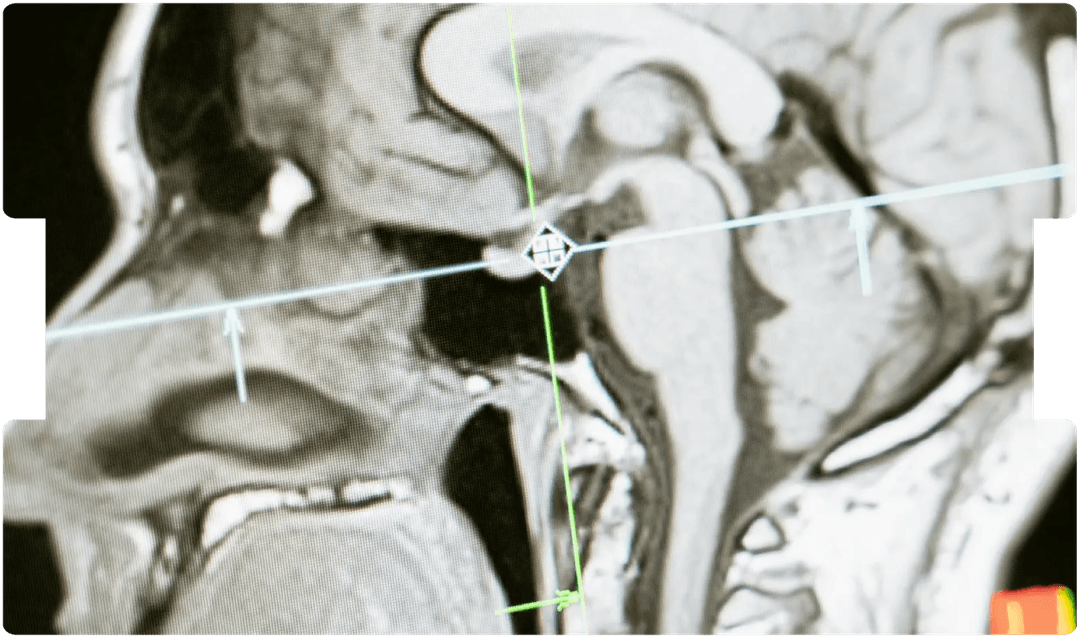

- mTBI

- Traumatic Brain Injury

- Brain Trauma

- Causation

- Brain Imaging Litigation

- Neurological Litigation

- Neurology